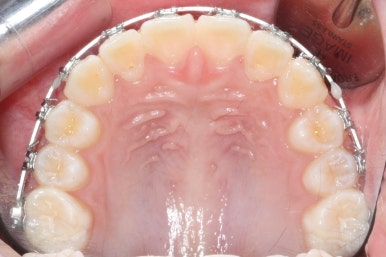

영구치도 이제 거의 다 나왔고 삐뚤한 다른 부분도 전체 메탈장치를 붙였습니다.

장치는 윗니부터 붙였습니다.

입안에 장치가 있다보니 불편할 수 있는데요. 이물감을 최소화 하고자 이동을 해야 할 양이 적은 아랫니들은 천천히 장치를 붙이기로 했습니다.

아래쪽에도 이제 장치를 전부 부착했습니다.

한 쪽의 송곳니는 제위치로 벌써 자리를 잡았네요.

장치를 부착한 후에 순차적으로 변화가 나타나는 모습입니다.

총 4장의 사진 동안 경과한 시간은 불과 6개월 입니다. 헤드기어를 통해 사전에 작업을 해뒀기 때문에 이후 연산동덧니교정 과정은 편해진 것이죠.

윗니만 6개월이 지난 모습입니다.

치열이 매우 가지런해졌죠. 이 후에는 특이사항 없이 종료가 되었습니다.